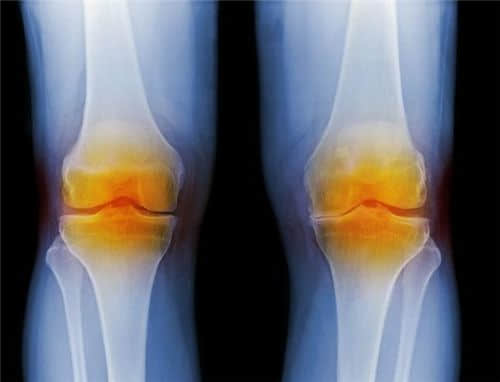

滑膜炎是一种很常见的骨科疾病,滑膜炎多发于青少年和老年人,不过对于年轻人和老年人患有滑膜炎的病因也是有区别的,滑膜炎对身体危害比较大,身体中关节的损伤和退变是造成滑膜炎的主要因素。尤其是当孩子出现滑膜炎症状时一定要注意,否则后患无穷。

膝关节的存在就是为了帮助人类完成行走和运动的,一旦受损,将会对生活、心理造成巨大的伤害,下面就来说说常见的日常护理。